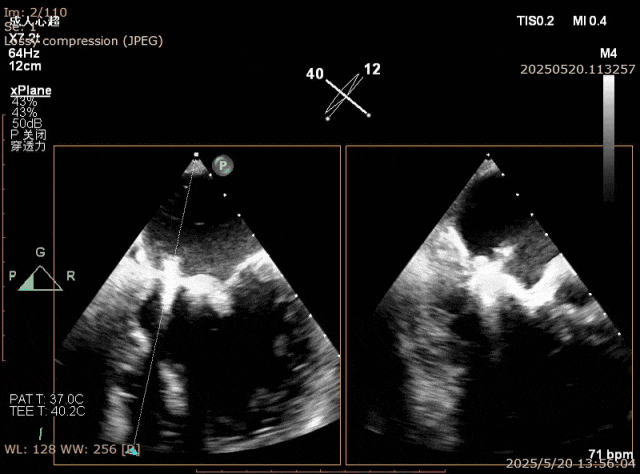

TEER手术时,有时候第一个夹子释放后因为腱索缠绕或者夹合不均匀导致夹子出现歪斜,这种歪斜可能导致瓣叶受力不均匀导致瓣叶损伤或者夹子脱落,若能纠正理论上会更好。这种情况下,可以使用第二个夹子的输送杆的将第一个夹子捋直,然后肩并肩植入第二个夹子进行纠正。操作时第二个夹子到达心室后需要先反转夹子,然后输送杆逐步靠近第一个夹子,不能用靠得太近使得夹子被挤压平移导致第一个夹子脱落,然后正转关闭夹子进行捕获夹合(图11-15)。

图12. P2大脱垂病例植入第一个夹子后出现夹子歪斜晃动大

图13. 第二个夹子关闭时可将第一个夹子卡入

图14. 反转夹子用输送杆将第一个夹子捋直

图15. 最后结果,双夹比翼双飞